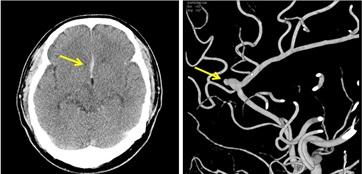

▲뇌동맥류파열.(좌)출혈부위 CT 사진 (우) 뇌동맥류 촬영 사진(국민건강보험 제공)